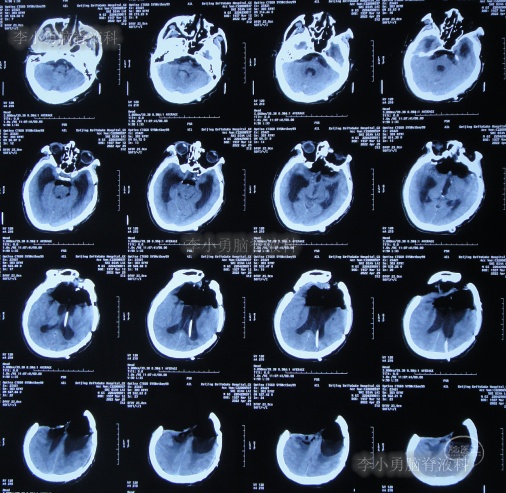

脑室腹腔分流术后7天即2012年10月23日,患者突发意识丧失、双眼上翻伴头部抖动近20分钟后自行缓解,查头颅CT(图-3)后考虑为“颅内感染”。

图-3:2012年10月23日头颅CT

脑室腹腔分流术后11天即2012年10月27日,进行了脑室腹腔分流管腹腔端外置术(图-4),术中可见清亮脑脊液流出。

图-4:2012年10月27日头颅CT

治疗期间给予腰穿脑脊液检查未见细菌,但白细胞、蛋白偏高,体温仍间断升高,最高38.6度,期间查头颅CT示脑室仍有扩张(图-5)。

图-5:2012年10月30日头颅CT